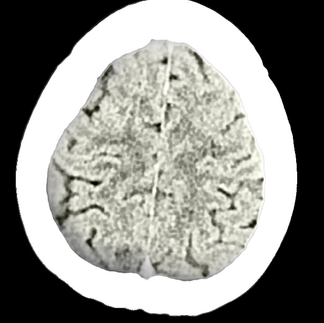

Our unique designs feature actual CAT scan photographs from our founder's CT scan, capturing the real, raw visual of what battling mental health struggles can look like.

Key Features: Authentic Imagery: Each piece in this collection showcases genuine CAT scan images of the brain, offering a stark, honest portrayal of the neurological impact of depression. These images are sourced directly from our founder’s personal CT scans, underscoring the reality of mental health challenges.